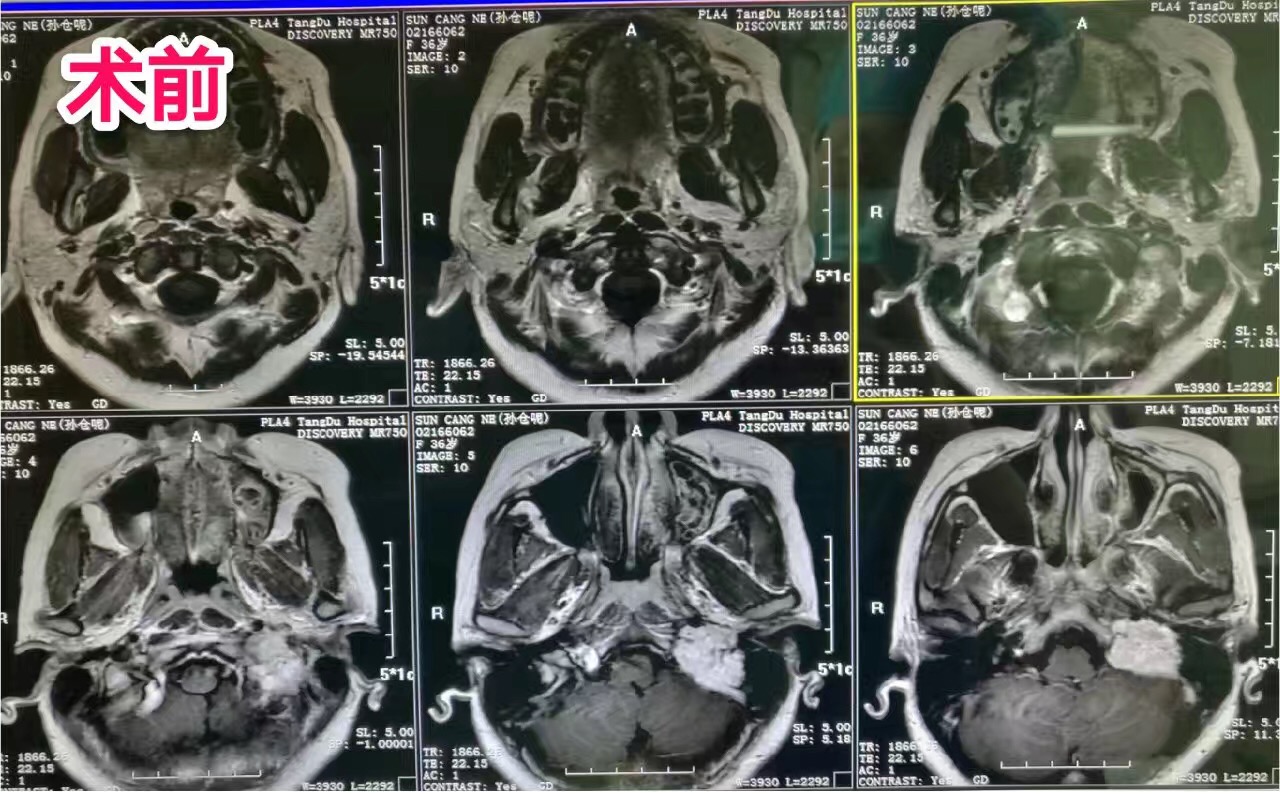

经岩迷路下入路切除颈静脉球瘤手术病理命名:鼓室球瘤,颈静脉球体瘤